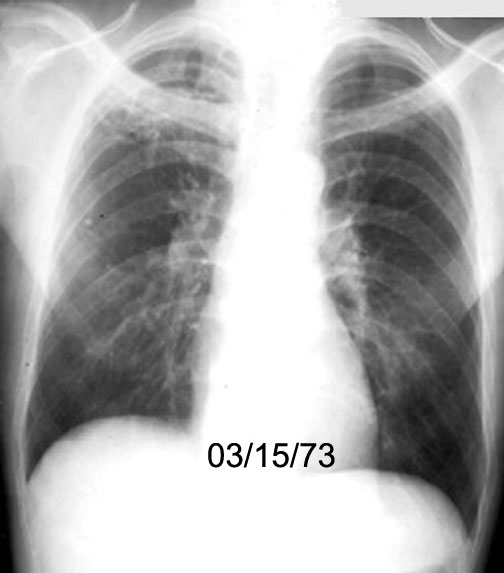

Case 9

Follow up